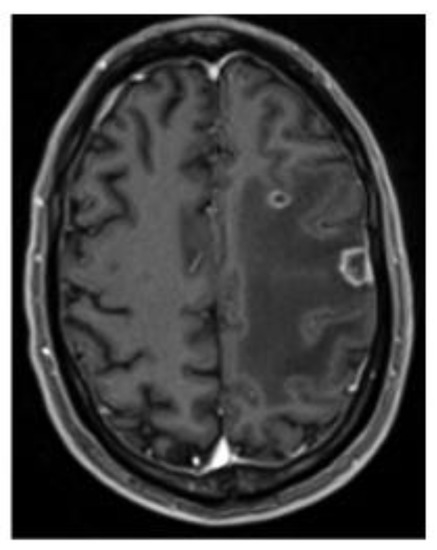

2. Case Presentation